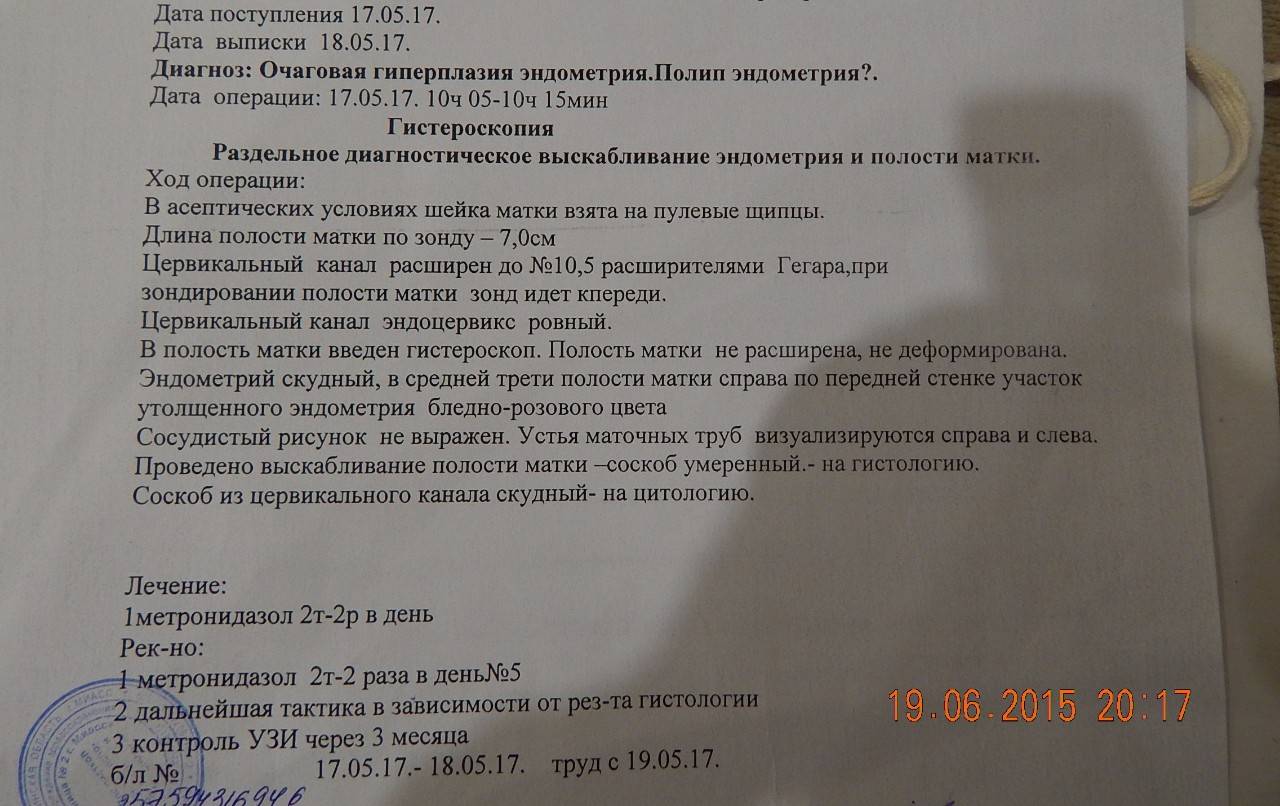

Медицинская диагностика: Гиперплазия эндометрия на УЗИ